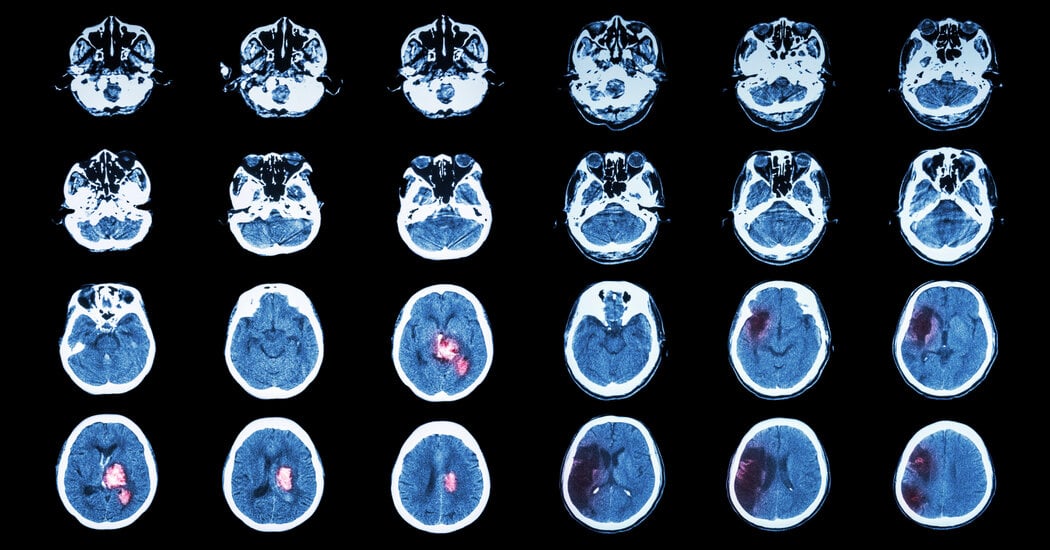

A Stanford-led study tests SAINT (Stanford Accelerated Intelligent Neuromodulation Therapy), a five-day, high-precision, noninvasive brain-stimulation treatment for treatment-resistant depression. In the trial, about half of the 24 participants receiving SAINT remitted by one month, compared with about 21% in the placebo group. SAINT uses rapid magnetic pulses targeted at the left dorsolateral prefrontal cortex via ten 10-minute sessions per day, delivering treatment faster and with greater precision than conventional TMS; the FDA cleared SAINT in 2022 and it’s offered at about 17 US clinics, though costs range roughly $16,000-$30,000 and insurance coverage varies. EEG data hint at biomarkers that could help predict who benefits, but more diverse studies are needed to confirm durability and broader applicability.